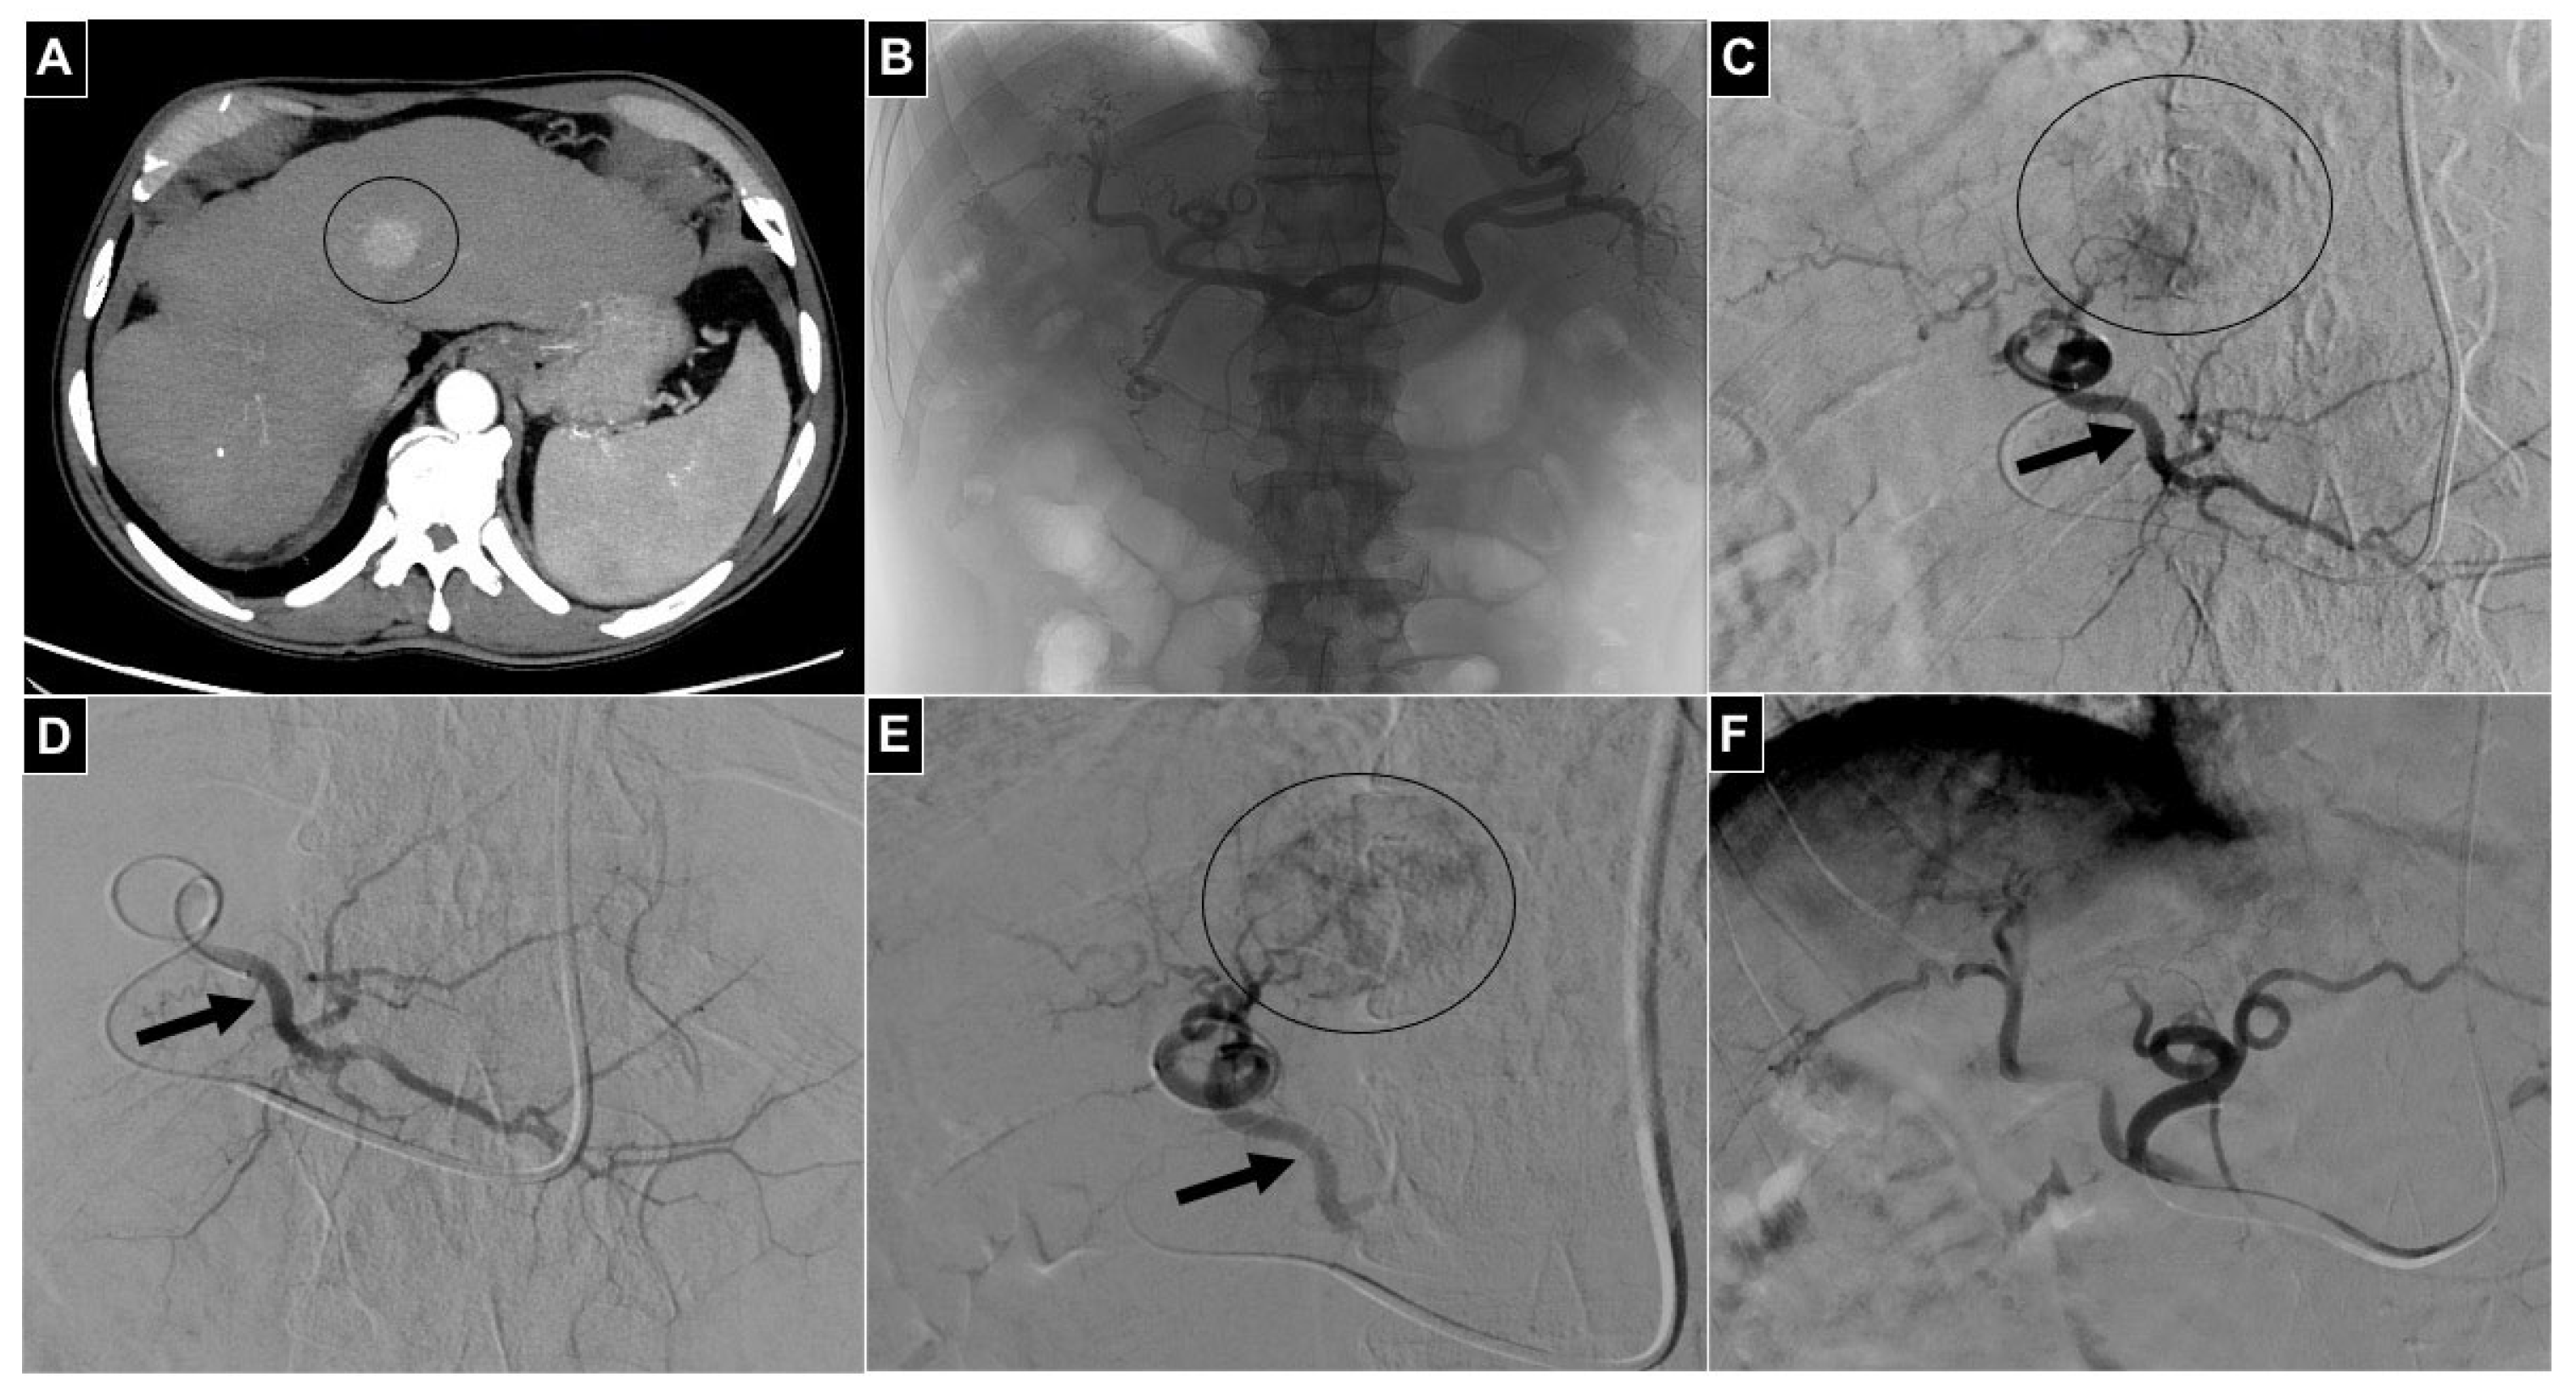

| 4 TARE | HCC | 2 Phrenic a. 2 Intrahepatic segmental a. | Intrahepatic a. | 99mTc MAA |

| 10 TACE | 8 HCC 2 CCC | 8 Intrahepatic segmental a. 2 Left gastric a. | Intrahepatic a. | Lipiodol-doxorubicin Preloadable chemiotherapic beads Embocept-S®-doxorubicin |